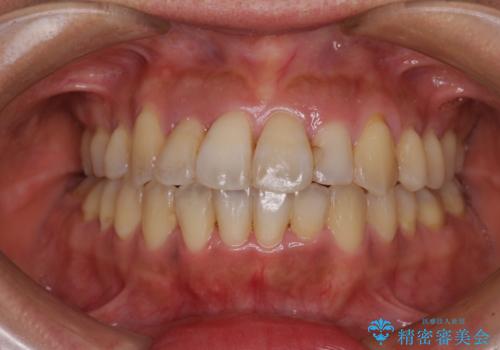

前歯のデコボコと深い咬み合わせ インビザラインできれいに改善

- 前歯のデコボコと下の前歯が隠れてしまう咬み合わせを気にして来院された患者様です。

インビザラインによる上下歯列の拡大と、IPR(歯と歯の間を削る)にるスペースの獲得により、口元のデコボコとディープバイトを改善することとしました。

インビザラインは、装着していない時間がどれだけ短いかが、治療期間を大きく左右します。こちらの患者様は1日22時間以上、毎日欠かさず装着してくださったため、1年弱という短期間で満足のいく歯列に整えることができました。